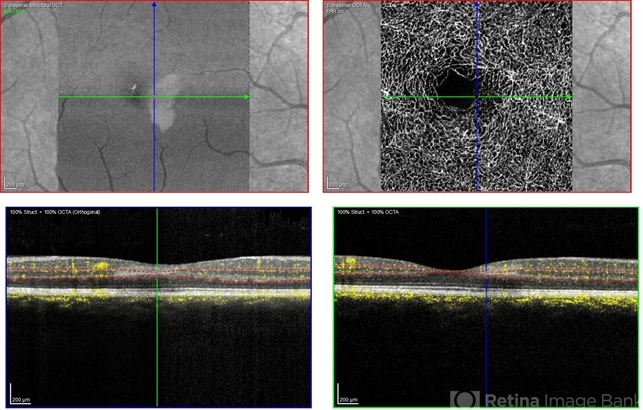

- paracentral acute middle maculopathy, OCTA

- OCT-A of a 30 yo female with PAMM OD.